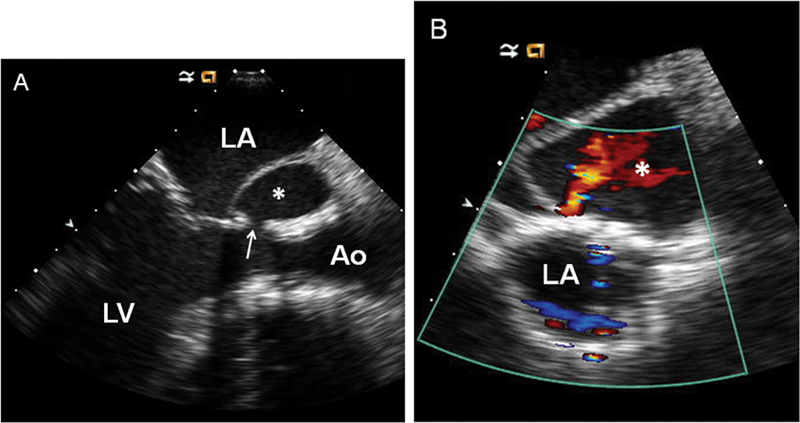

فحوصات تشخيصية لبعض امراض القلب والشرايين التاجية